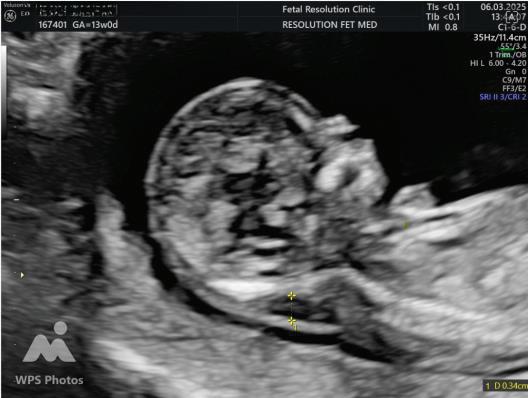

2. NUCHAL TRANSLUCENCY (NT) SCAN

• Done @11–13+6 weeks.

• CRL 45–84 mm.

• This is the cornerstone of first trimester screening.

NASAL BONE:

Hypoplasia defined as length <2.5mm.

Absent METHOD OF MEASUREMENT

• Mid saggital plane.

• Good face profile.

• At 45 degree angle with imaginary line from forehead to chin.

• 3 echogenic lines.

• Absent nasal bone is more common if The gestation is 11 than 13 weeks. The fetal nuchal translucency is high. The mother is Black.